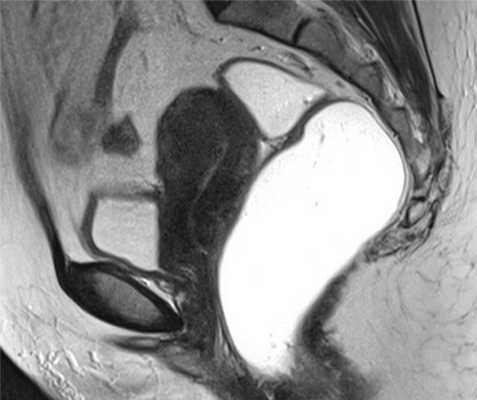

![]()

Рис.7 Сокращения матки, имитирующие аденомиоз: а) и b) сагиттальные T2 взвешенные изображения, гитпоинтенсивные полосы, перпендикулярные к переходной зоне, исчезающие/изменяющиеся через несколько минут, представляют собой физиологические сокращения матки.

Рис.8 Псевдо-расширение эндометрия: сагиттальные T2 взвешенные изображения, утолщение переходной зоны с полосатыми участками высокой интенсивности сигнала, расходящимися от эндометрия по направлению к миометрию, имитирующими инвазию рака эндометрия.